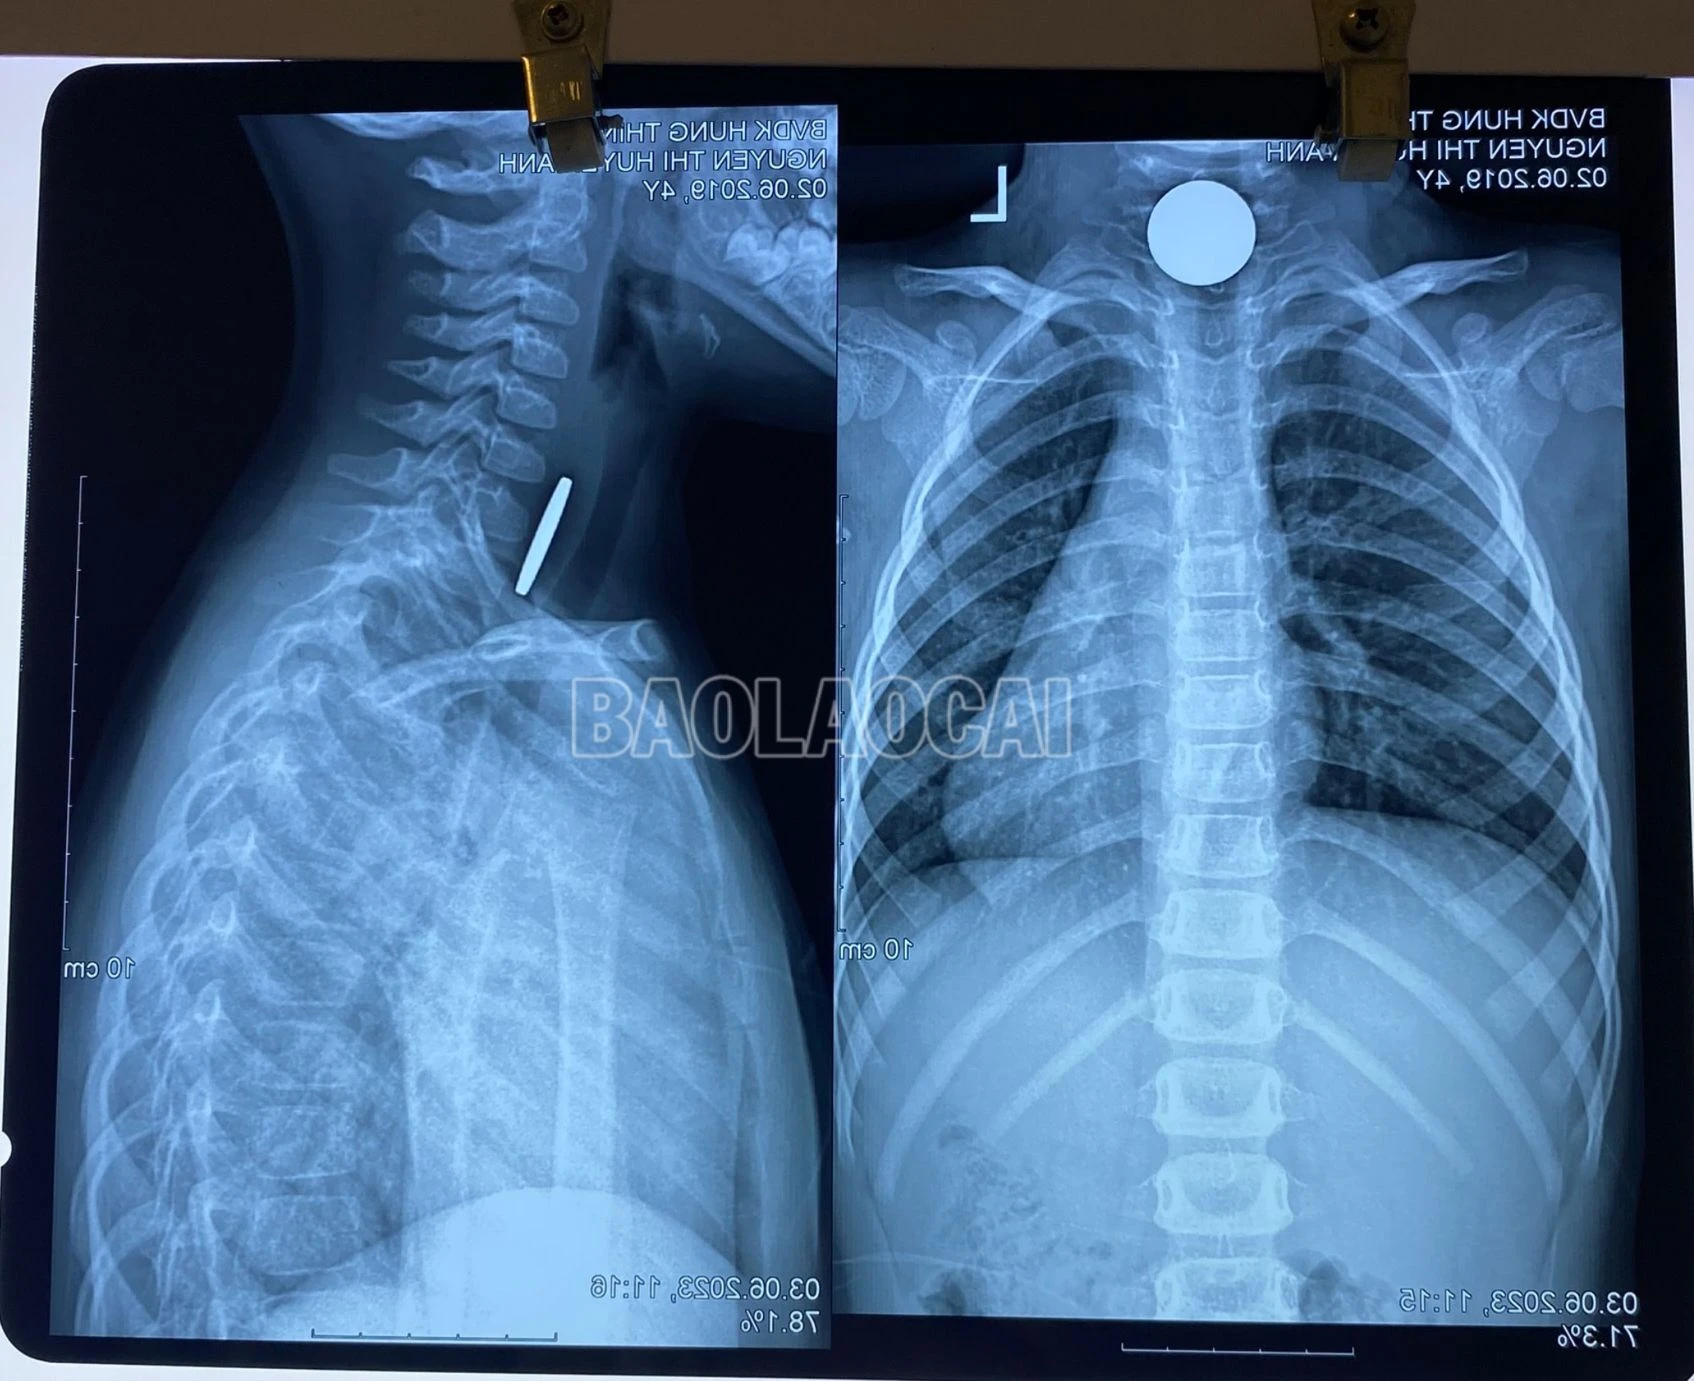

Ngay sau đó, trẻ được chụp X-quang chẩn đoán, kết quả cho thấy dưới cơ thắt nhãn hầu có dị vật là 1 đồng xu. Các bác sỹ đã hội chẩn và chỉ định thực hiện gây mê, gắp dị vật thực quản qua nội soi bằng kìm cá sấu. Đồng xu được gắp ra thành công có đường kính khoảng 22 mm, sức khỏe trẻ hồi phục tốt.